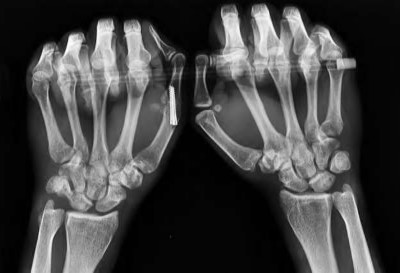

volar tenderness along the flexor sheath

Patients commonly present 24 to 48 hours after onset of symptoms. The standard of care is “urgent surgical drainage” to avoid tendon scarring or necrosis with subsequent impairment of finger function followed by intravenous antibiotic administration.

According to Hand Surgery Update 3, open sheath irrigation has been replaced

largely by closed sheath irrigation. These authors cite a retrospective study that showed no statistical difference in resolution of infection using open sheath irrigation or closed sheath irrigation, however, there was a trend towards more frequent complications and reoperations in the open drainage group.

Lille et al reviewed the records of 75 patients with pyogenic flexor tenosynovitis and found that there was no difference in outcomes between those who received intraoperative irrigation only versus those receiving intraoperative irrigation and continuous postoperative irrigation.